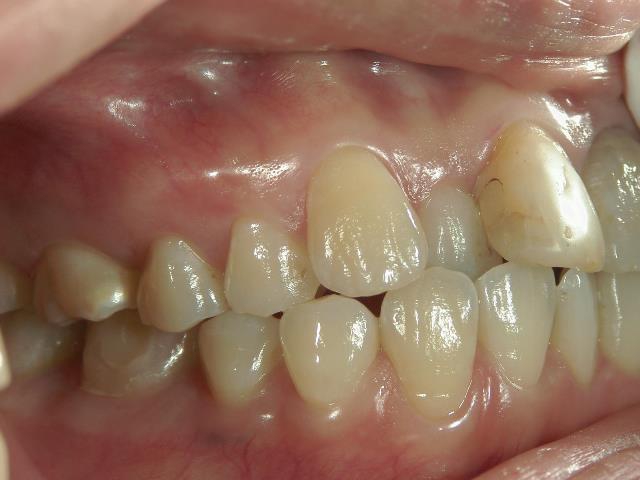

no.37_7548_治療前_右.JPGno.37_7548_治療前_正面.JPGno.37_7548_治療前_左.JPG

矯正歯科 治療後  スペース確保の為、 2番抜歯